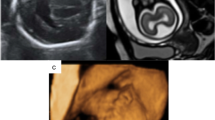

Examples of group C—unilateral CFA as defined in this paper. C1 (a)—axial images of a foetus (25 gestational weeks) with a unilateral area of dysmorphic brain (arrows). There is abnormal low T2-weighted signal in the affected (left) hemisphere. The foetus also had agenesis of the corpus callosum and interhemispheric cyst. C2 (b)—axial and coronal images of a foetus (32 gestational weeks) with unilateral excessive sulcation/gyration (numerous, small gyri) in part of the left hemisphere (arrows). C3 (c)—axial and coronal images of a foetus (35 gestational weeks) with unilateral poor sulcation/gyration of the left hemisphere (arrows), that is hypoplastic. Unevenly diffuse reduced signal within white matter is present. The foetus also had a Dandy-Walker malformation (not shown). C4 (d)—axial and coronal images of a foetus (21 gestational weeks) with unilateral trans-mantle cleft in the left hemisphere (arrows). The cavum of septum pellucidum is absent. C5 (e)—axial and coronal images of a foetus (18 gestational weeks) with unilateral focal distortion in the form of an early abnormal sulcus in the left hemisphere (arrows). This foetus also had hypoplasia of the corpus callosum. C6 (f)—axial and coronal images of a foetus (26 gestational weeks) with unilateral enlarged right hemisphere (arrows), which is also generally malformed